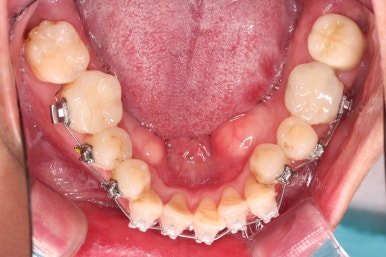

교정 10개월째인데, 악궁형태 많이 좋아졌고, 가지런한 느낌도 많이 좋아졌습니다.

초기 단계의 주안점은 아랫니와 악궁과 어울리는 윗니 악궁의 형태를 만들어 주는 것이고요.

악궁확장장치를 사용하지 않은만큼 철사의 형태를 잘 잡아가면서 악궁 형태를 개선시킵니다.

✅ 악궁확장도 하지 않기로 했습니다.

어쨌든 이번 환자분은 적극적인 악궁확장 장치까지는 필요 없었고, 브라켓-와이어로만 부산구순구개열교정으로 개선해 보기로 했습니다.